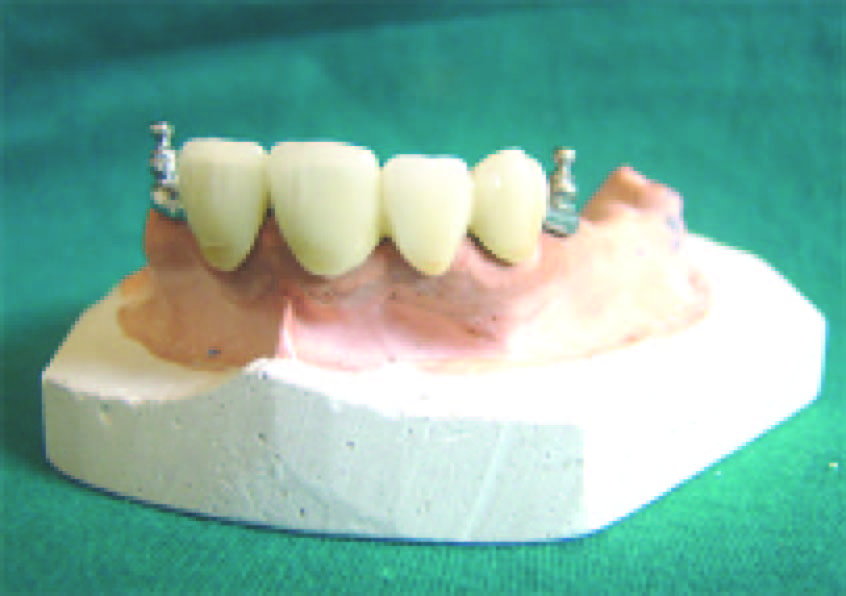

The treatment planning for prosthetic rehabilitation for this patient was made after considering the age of the patient, multiple missing teeth and long standing partial edentulism. For the purpose of improved aesthetics and elevated psychological acceptance of the prosthesis by the patient, precision attachment retained interim removable partial denture was planned in the maxillary arch [5]. Due to poor periodontal condition of lower anterior teeth, a conventional clasp retained interim removable partial denture was planned for the mandibular arch [6]. The enlarged pulp chambers of the anterior teeth carried a risk of perforation during tooth preparation and hence 21, 11, 13 were root canal treated. Primary impressions of the upper and lower arch were made. Casts were prepared with type III dental stone. Temporary baseplates and wax occlusal rims were fabricated and a tentative jaw relation was carried out to confirm that adequate inter-arch space was available for fabrication of precision attachment retained prosthesis. Tooth preparation for porcelain fused to metal bridge was done on 21, 11, and 13 [Table/Fig-5]. Anatomic impression of the upper arch was made in putty elastomeric impression material and light body. Anatomic cast was prepared in type 4 dental stone. Porcelain fused to metal bridge was fabricated on this anatomic cast on the prepared abutments of 11, 13 and 21 [Table/Fig-6]. The extra coronal precision attachment that is the O-ring posts (male patrix) were incorporated distal to 13 and 21 in the porcelain fused to metal bridge [Table/Fig-7]. Following trial, finishing and polishing, this porcelain fused to metal bridge with the extracoronal precision attachments was cemented permanently in the patient`s mouth with Glass inomer cement on the abutment teeth 11, 13 and 21 [Table/Fig-8]. Functional impressions of the upper and lower arch were made and master cast was poured in dental stone type IV [7]. Jaw relation, try in and fabrication of the removable partial dentures in the upper and lower arches were then carried out sequentially. The female matrix namely the O-rings were incorporated into the upper partial denture in correspondence to the male patrix that is the O-ring posts [Table/Fig-9]. The removable partial dentures were inserted in the patient’s mouth after minor adjustments in the occlusion [Table/Fig-10,11]. The patient was educated about the usage and maintenance of the prosthesis. Follow-up appointment was scheduled after 3 months to study bone growth and plan for a definitive prosthesis.

O-ring incorporated upper partial denture and lower conventional removable partial denture,